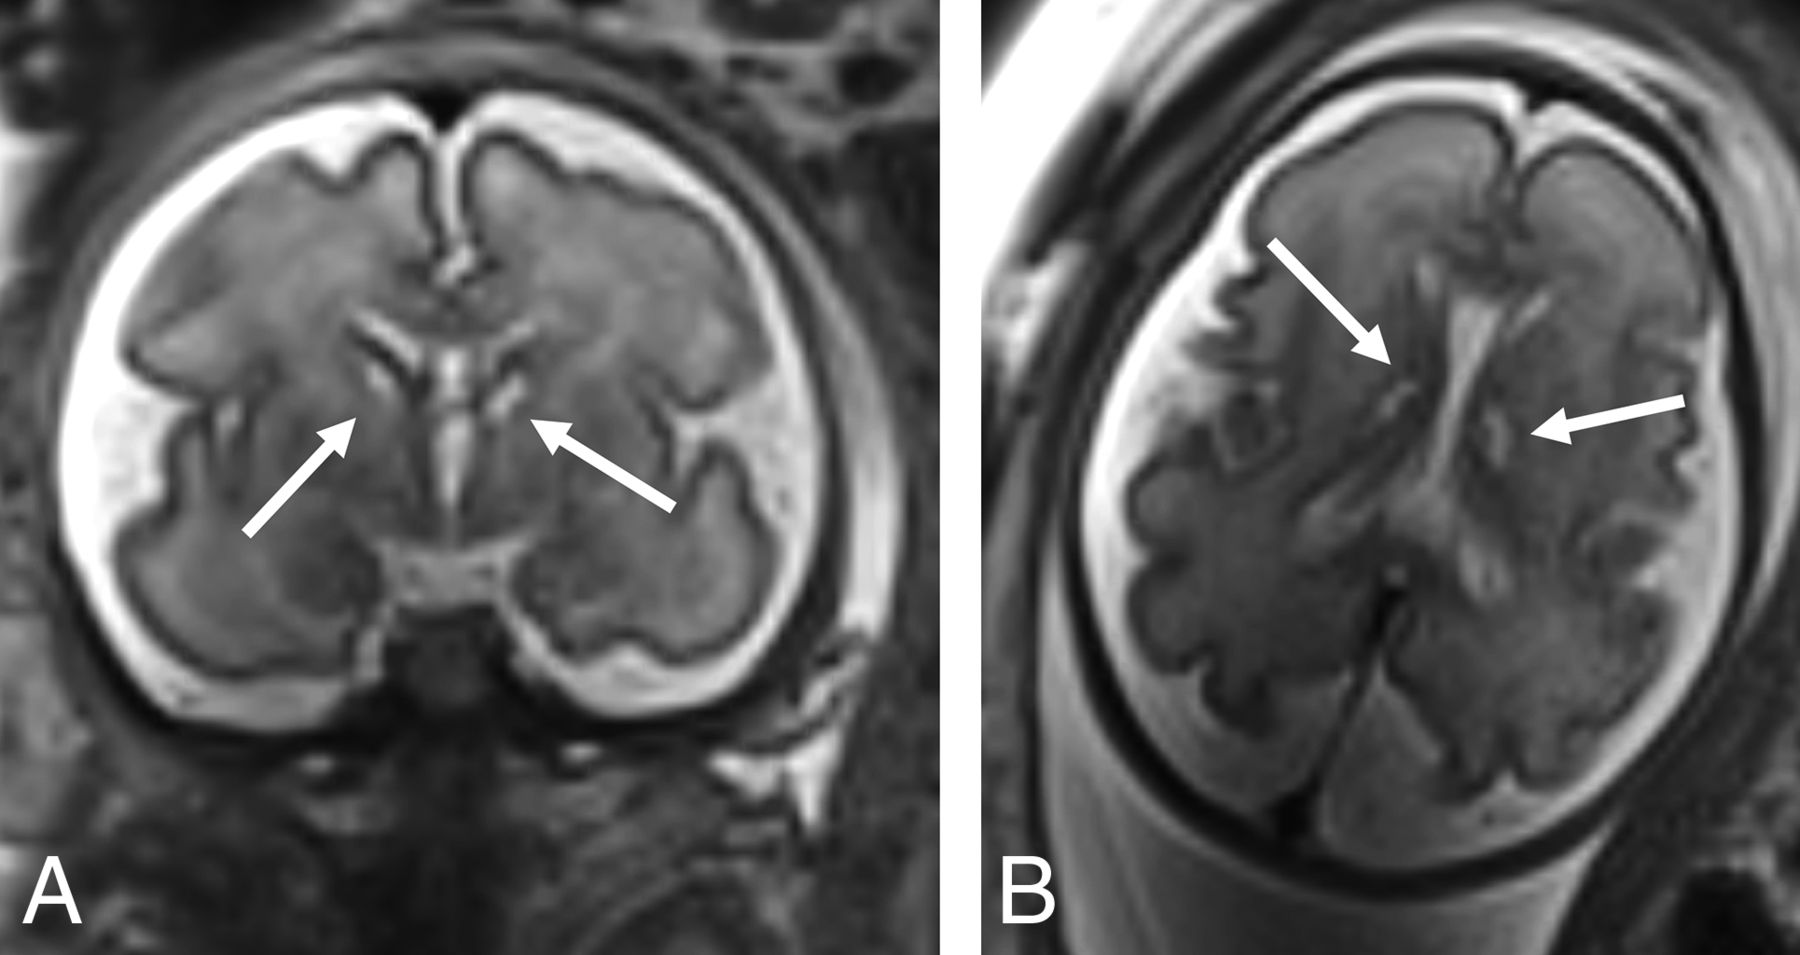

fbMRI revealed a normal sulcation pattern in all surviving fetuses following sIUFD. No acute brain infarction or parenchymal hemorrhage was noted in any of the surveillance third-trimester fbMRIs performed in the sIUFD group. One fetus (∼3.5% of the sIUFD group) showed bilateral caudothalamic cystic changes (Fig 3). No ventriculomegaly was observed, though 7 fetuses showed asymmetry of the lateral ventricles (compared with 5 in the singleton and 7 in the twins control groups). No cortical abnormalities, corpus callosum, septum pellucidum, or posterior fossa abnormalities were noted.

Coronal (A) and axial (B) T2-weighted images of a 30-week surviving twin following spontaneous sIUFD at a GA of 18 weeks, showing caudothalamic cystic changes (arrows).